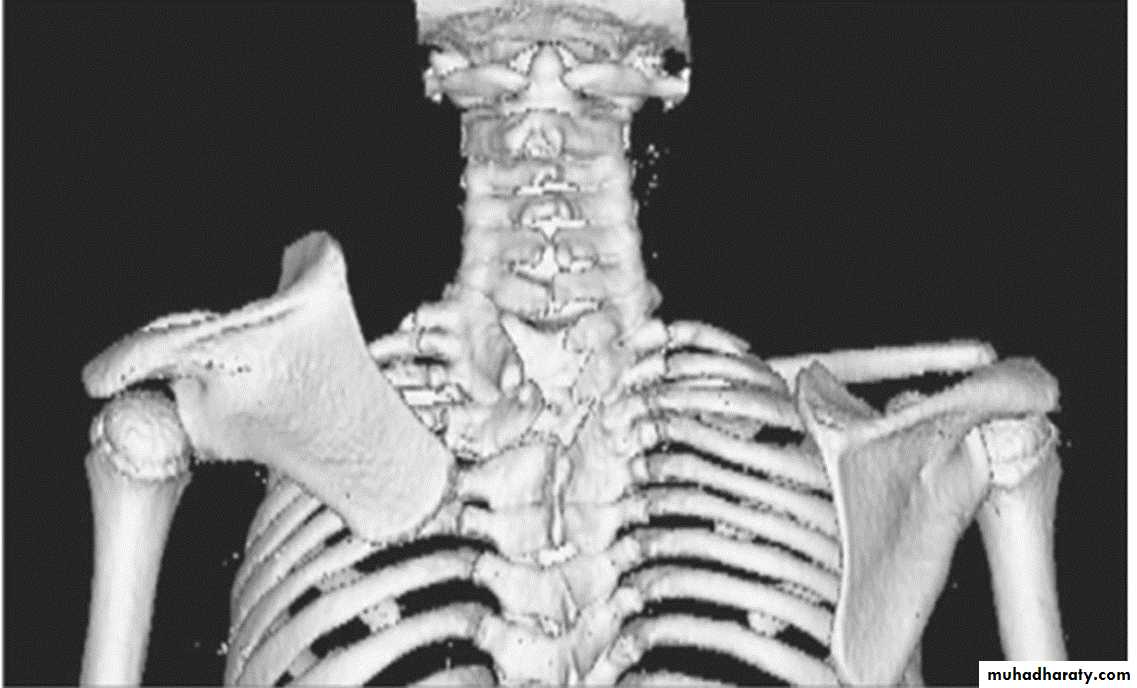

Ankylosing spondylitis-early

(A) Serrated marginsof sacroiliac joints and peri articular sclerosis.

(B) CT scanning demonstrates bilateral sacroiliitis